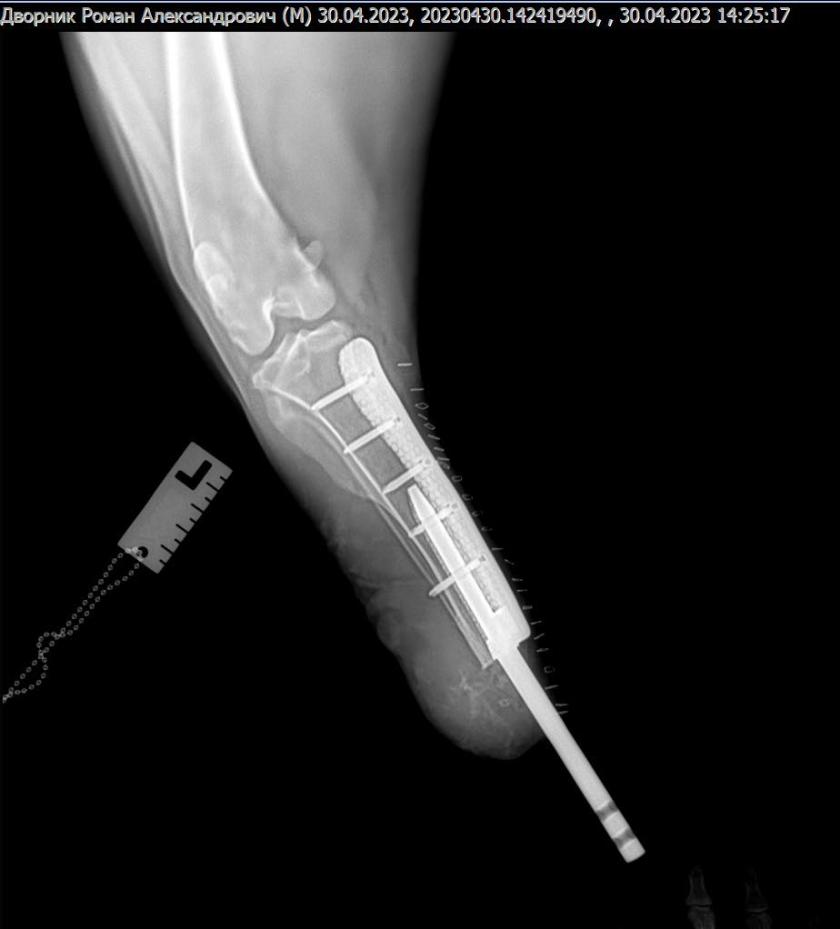

Хірург-травматолог Віталій Клубань з колегами провів операцію на базі Салтівської ветеринарної клініки — філіалу "Харківського ветеринарного госпіталя".

Пораненій тварині, яка перенесла травматичну ампутацію, вживили біоінтегрований протез.

"Сподіваємось на скоре одужання нашого паціента. Подяка власникам, що не кинули свого улюбленця в такі тяжкі часи. Розробка імпланту 3D metal tech!", — написав головний лікар Харківського ветеринарного госпиталю Віталій Клубань у фейсбуці.